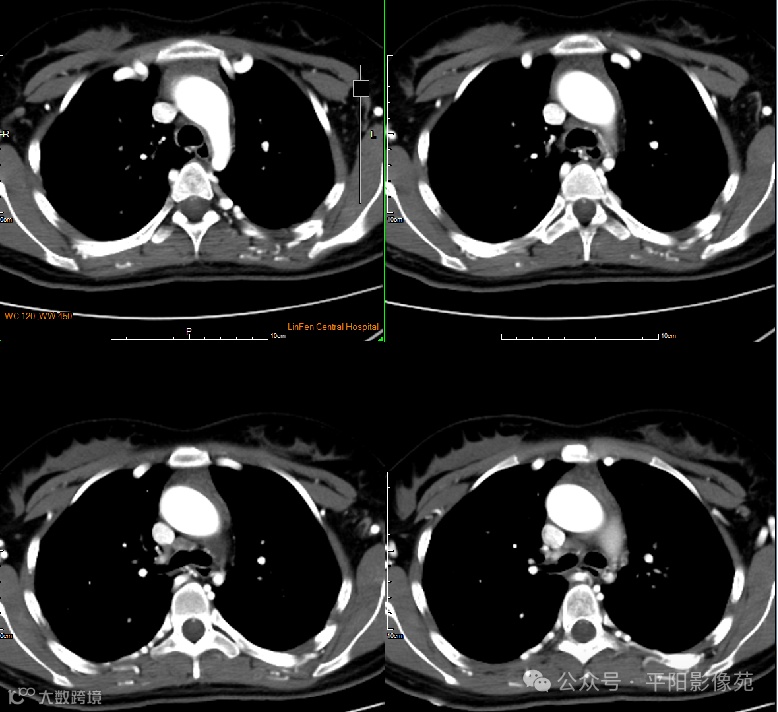

影像检查